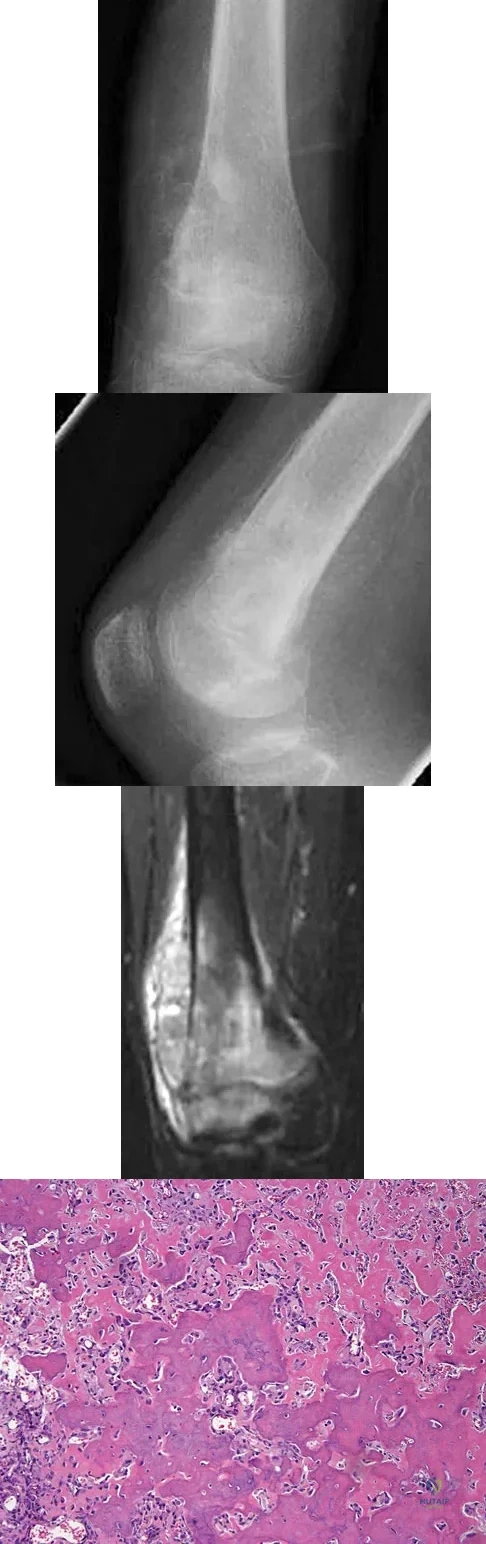

Question 37

A 12-year-old girl has had progressive left knee pain for the past 4 months. She reports that the pain is unrelated to activity, and she has no history of fever or recent infections. Examination reveals full range of motion of the knee but tenderness along the medial joint line. Plain radiographs and MRI scans are shown in Figures 39a through 39d. A biopsy specimen of the lesion is shown in Figure 39e. Treatment should include

Explanation